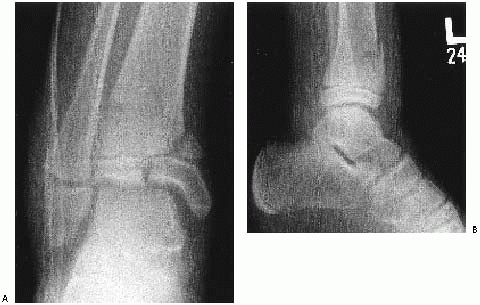

![]() |

FIGURE 26-2

Comminuted Salter-Harris type IV fracture of the distal tibia and displaced Salter-Harris type I fracture of the distal fibula produced by an inversion (shearing) mechanism in a 10-year-old girl. |

fracture of the tibia produced by a shearing (Fig. 26-2)

or crushing force might be more likely to result in growth arrest than